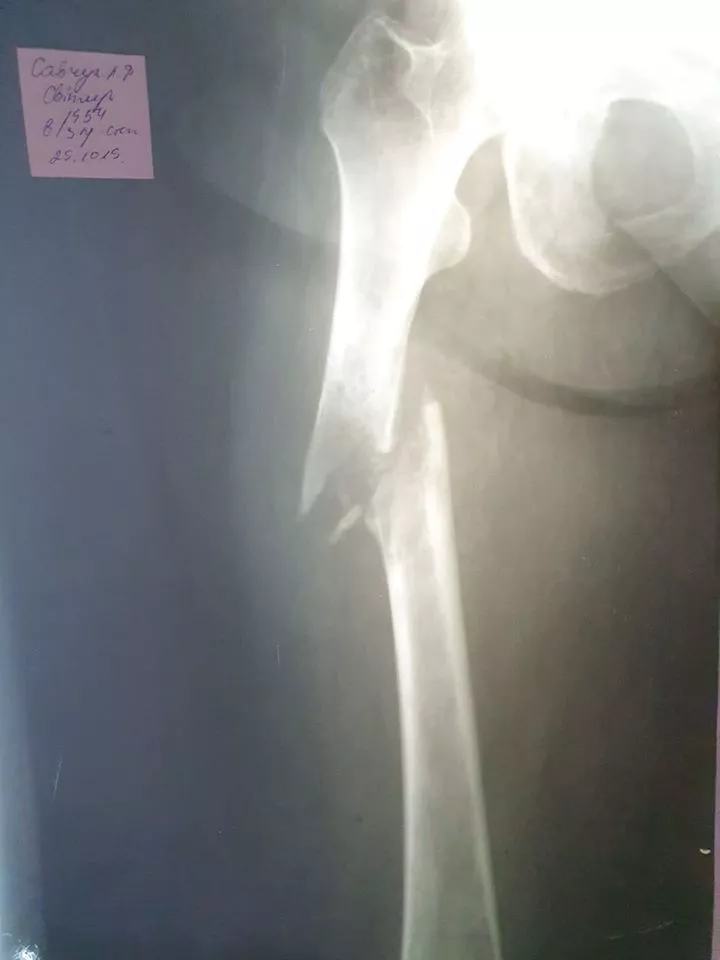

Любомльські лікарі вперше провели операцію онкохворій жінці з патологічним переломом стегна. ФОТО 18+

Вперше лікарі-травматологи Любомльської лікарні провели операцію жінці, яка мала онкологію з метастазами в кістки, та отримала патологічний перелом лівої стегнової кістки зі зміщенням. Попередньо обстеживши жінку, лікарі погодилися прооперувати її у Любомльській лікарні.

Ризики для проведення такої операції були чималі, оскільки 64-річна пацієнтка, жителька одного з сіл Шацького району, мала гіпертонічну хворобу, онкологію стегнової кістки та був ризик кровотечі під час операції.